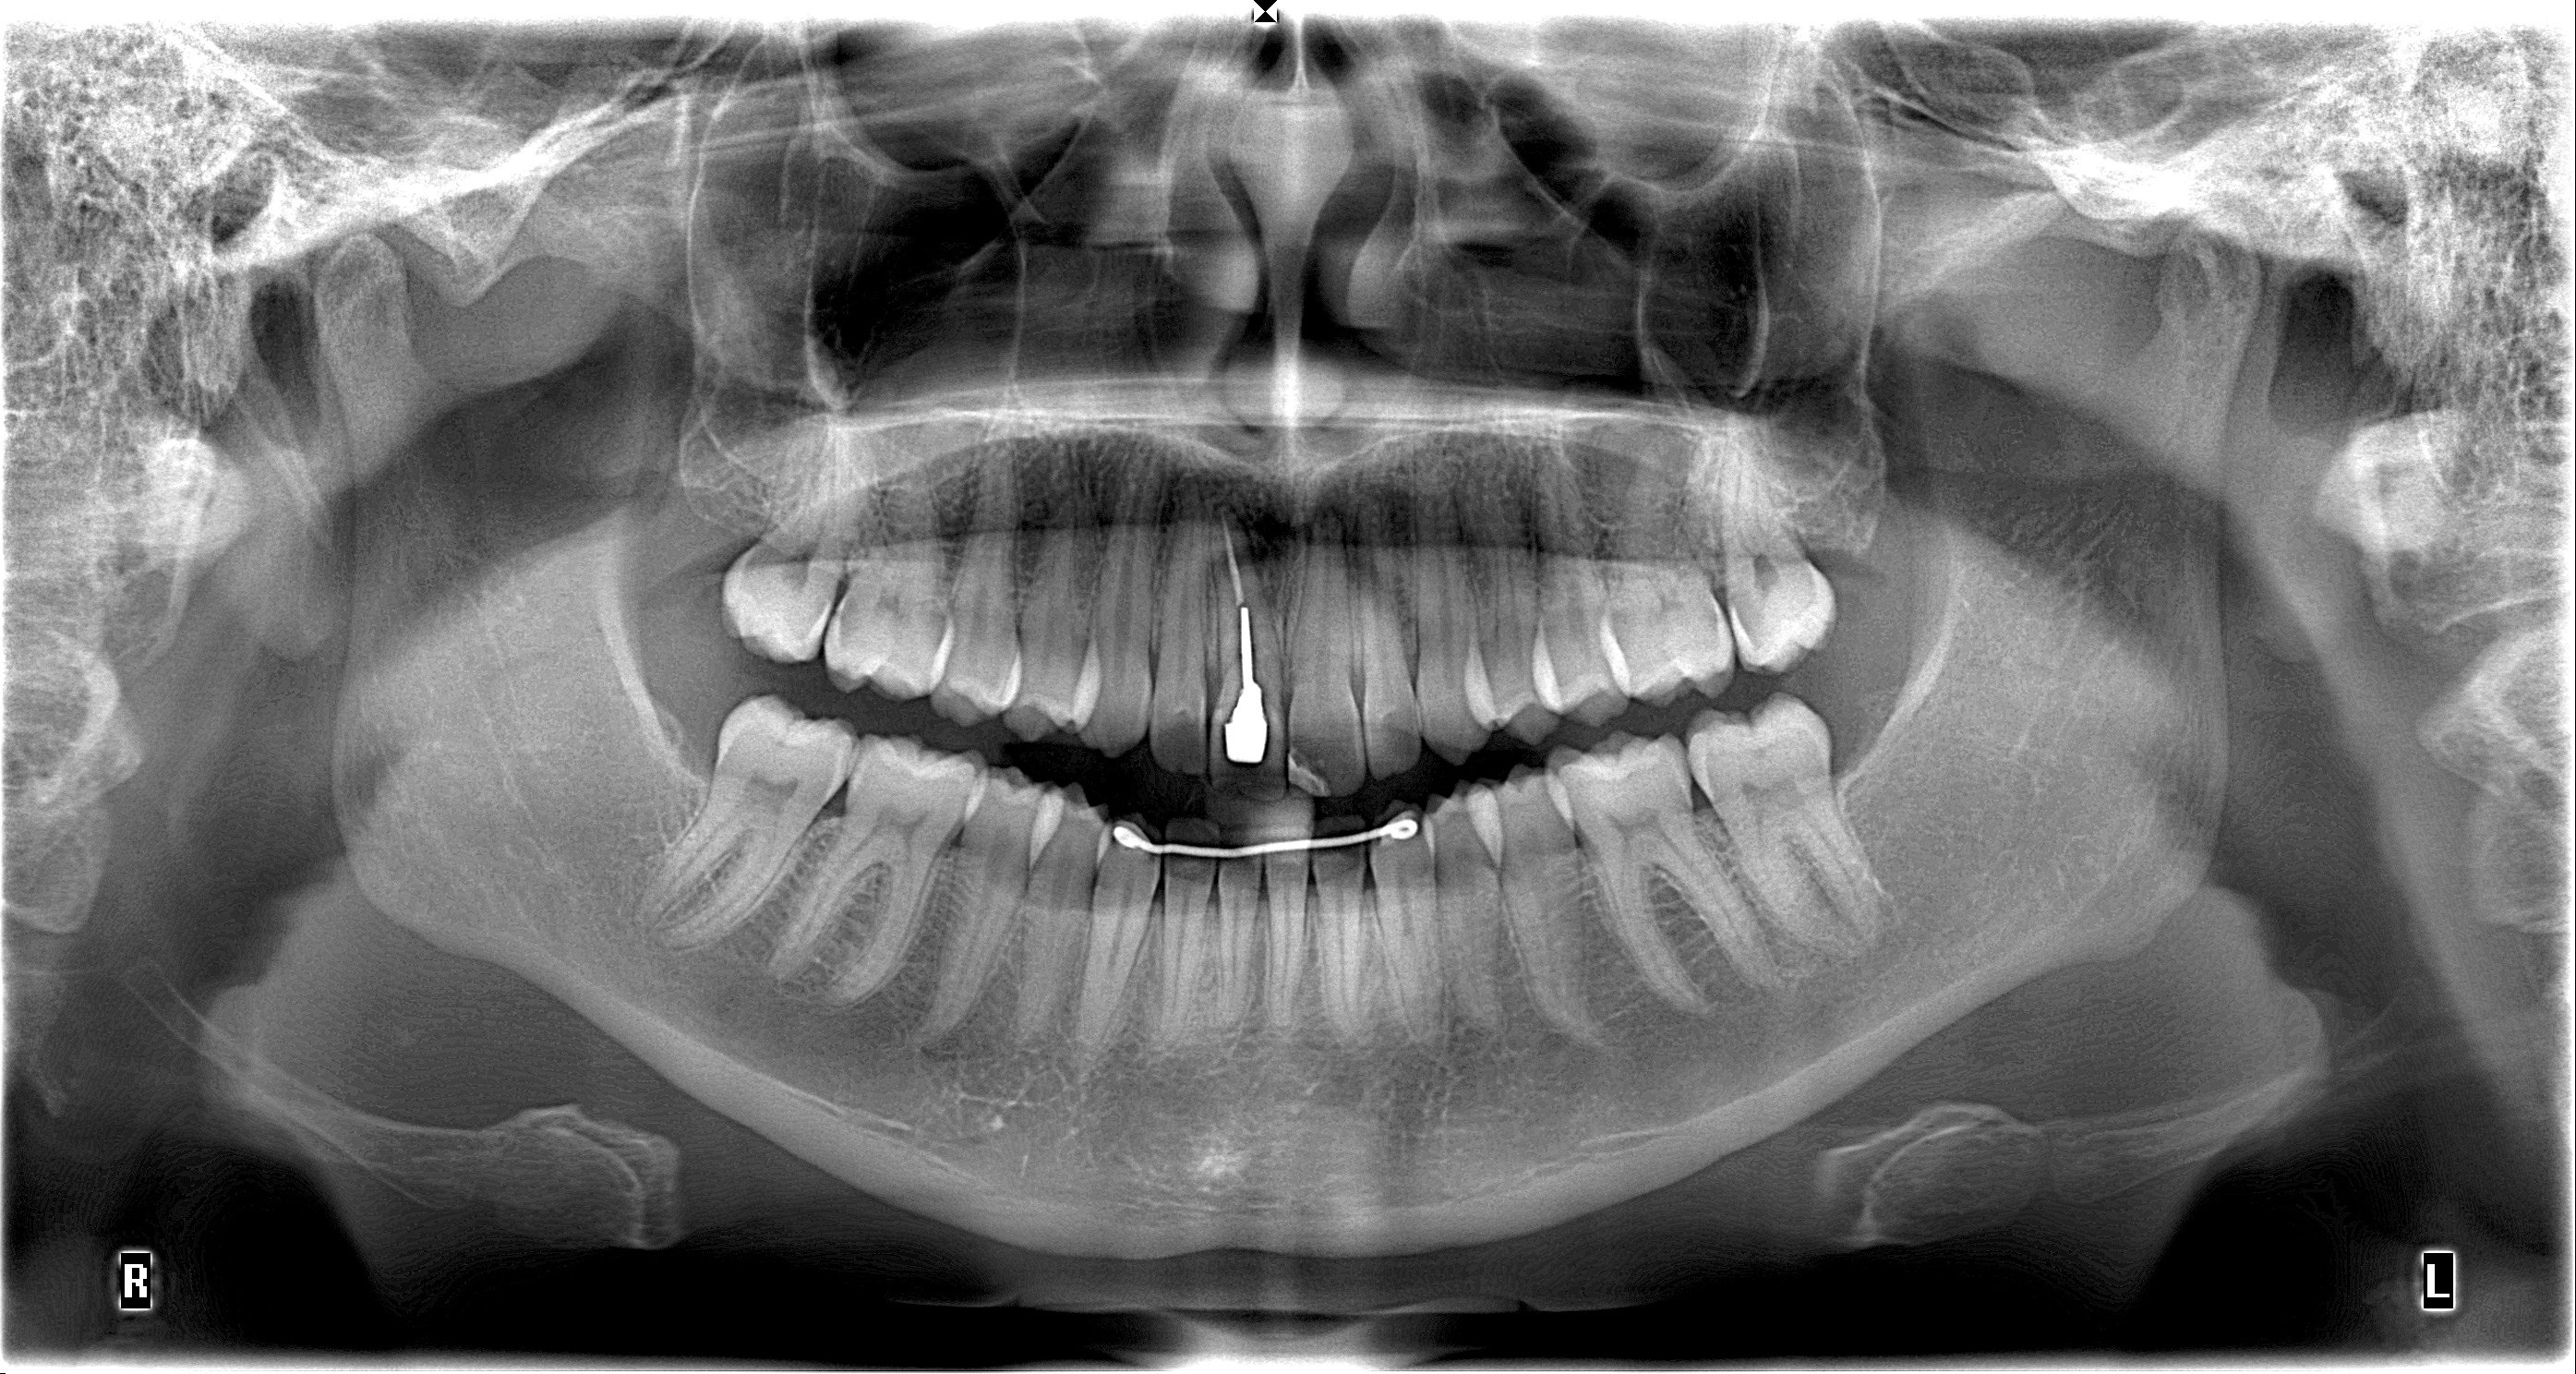

• Panoramique (Photo 2)

Avec la radiographie panoramique, on s’aperçoit que la dent 11 présente un traitement endodontique,

un inlay core et une couronne.